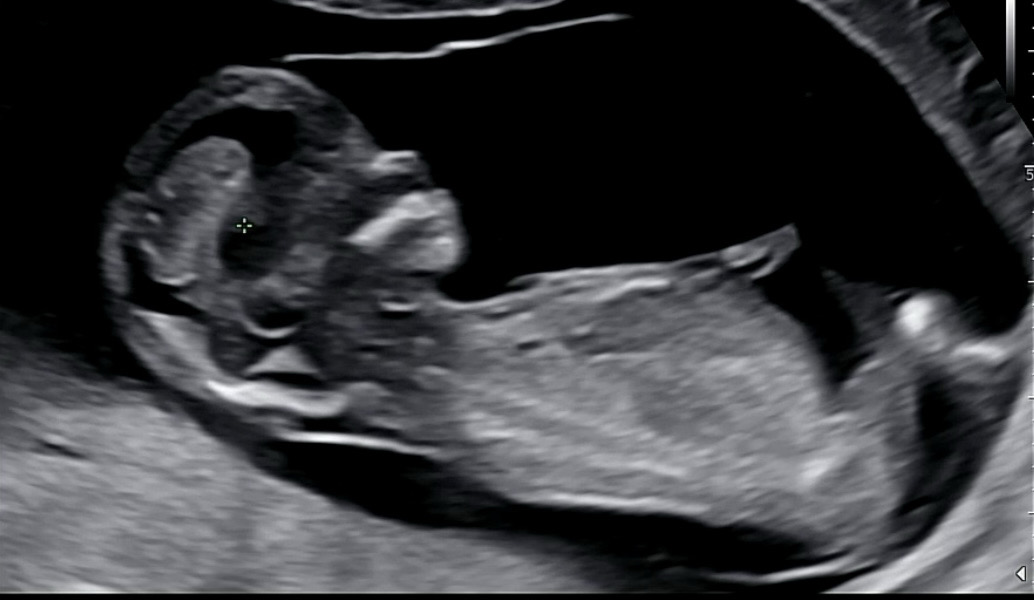

12주5일 각도법 고수님 한번만 봐주세요

아들딸 상관없지만. 궁금한거 어멀수 없네요 ㅎ사진이 안나온건지 저는 봐도 도저히 모르겠습니다.

어려운디 아들같아요

아들같아용